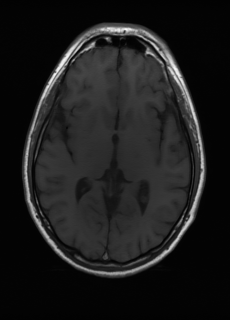

Sequence LR SISO MIMO MIMO tuned GT

λT1=2.90subscript𝜆subscript𝑇12.90\lambda_{T_{1}}=2.90 Refer to caption (a) 38.30/0.9484 Refer to caption (b) 45.03/0.9920 Refer to caption (c) 45.35/0.9926 Refer to caption (d) 46.70/0.9951 Refer to caption (e) PSNR/SSIM

λT2=2.44subscript𝜆subscript𝑇22.44\lambda_{T_{2}}=2.44 Refer to caption (f) 29.78/0.8990 Refer to caption (g) 35.43/0.9720 Refer to caption (h) 35.93/0.9752 Refer to caption (i) 37.05/0.9809 Refer to caption (j) PSNR/SSIM

λflair=7.82subscript𝜆𝑓𝑙𝑎𝑖𝑟7.82\lambda_{flair}=7.82 Refer to caption (k) 41.24/0.9412 Refer to caption (l) 44.54/0.9850 Refer to caption (m) 45.66/0.9885 Refer to caption (n) 46.15/0.9891 Refer to caption (o) PSNR/SSIM

Figure 5: Visual comparison of different recovery methods on real data